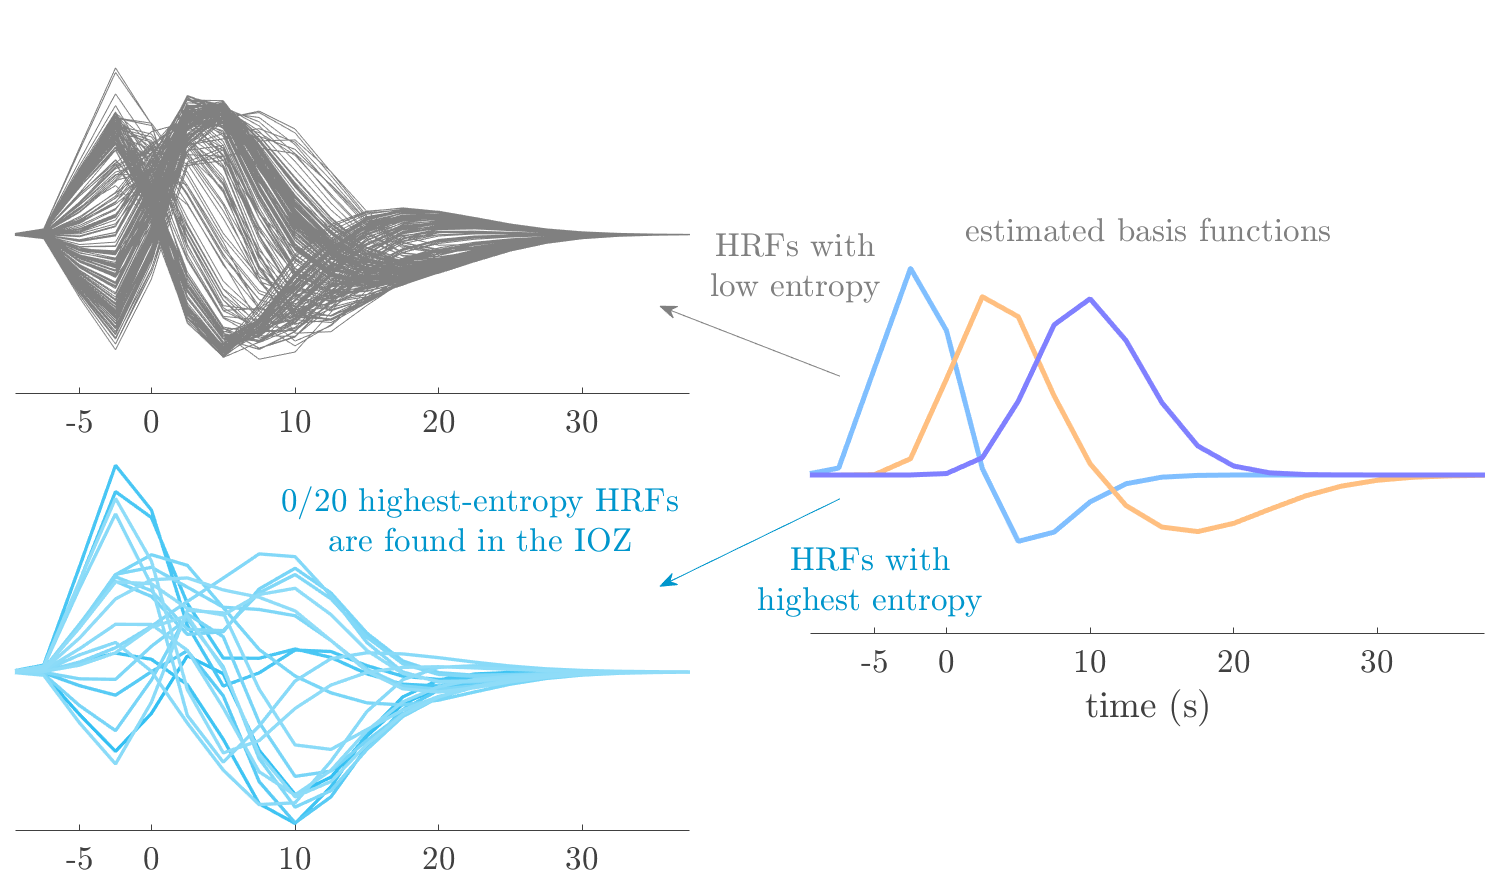

Patient 2

We analyze the solution with sources, and show the results in Figure 3 and 4. As for patient 1, we found a source which is strongly correlated to the MWF envelope, and which had a mostly low-frequency behavior characteristic for spikes. The topography is mostly uninformative, and does not clearly correspond to the patient’s clinical data. The third source is mostly present at both sides of the head, is very sparsely active in time, and has a high-frequency content: this is most likely an artifact due to the neck muscles. Again, there is one of the highest-entropy HRFs which belongs to a ROI in the IOZ. Now, the waveform is clearly resolved from the other HRFs, through the strong initial dip (before 0 seconds). Such a dip is sometimes observed in HRFs, but its underlying physiological mechanism is not yet fully understood. It is possible that this dip reflects altered vascular autoregulation near the IOZ (cfr. the explanation in the Section 1 of the main text), or a rapid depletion in oxygen due to IED generation (before the IED becomes visible on the EEG). Figure 4 furthermore shows that the IED-related component is significantly active in parts of the IOZ, and deactive in others. As mentioned earlier, this deactivation may or may not be due to errors in sign correction. Interestingly, the ROI with the high alteration in neurovascular coupling is distinct from both the activated and deactivated ROIs.